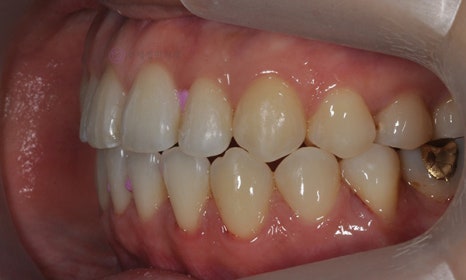

다음 케이스 역시 위 아래 치아의 중심선 차이가 있으며, 덧니 및 반대교합이 관찰되었습니다. 위 치아의 중심선도 얼굴의 중심선과 일치하지 않고 우측(사진 상 왼쪽)으로 틀어져 있었습니다. 본 환자는 발치를 하지 않고 치아를 뒤로 이동시켜서 치아의 중심선도 맞추고 얼굴의 중심선과도 맞추었습니다.

2020.1

교정 마무리 후 위 치아의 중심선은 얼굴의 중심선과 일치하였으며, 위 아래 치아의 중심선도 일치하였습니다.